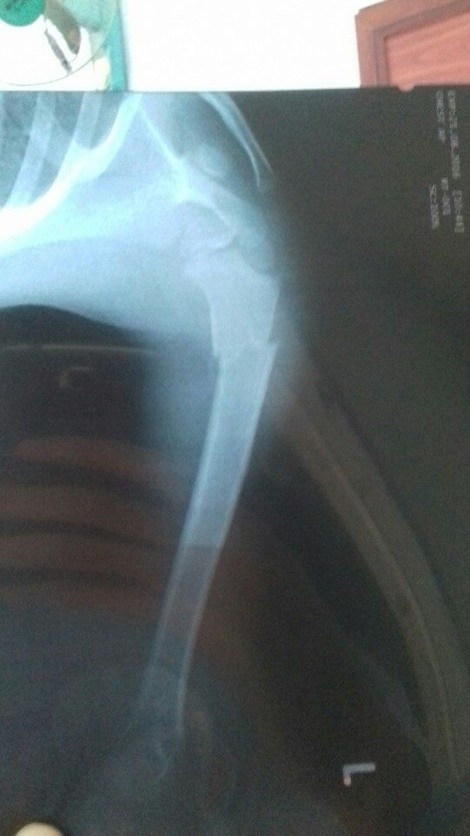

Phim X-quang cho thấy rõ ràng vị trí gãy xương trên cánh tay trái

Lần khám thứ 3 vào ngày 16.8, bác sĩ V.D.K lại chẩn đoán cháu bé chỉ bị trật khớp, bong gân, giãn khớp và dây chằng. Lần khám thứ 4, khi tay trái của cháu bé không thể nhấc lên cao và lủng lẳng như không xương bả vai, vị bác sĩ Minh N. – người khám lần đầu tiên cho chụp X-quang lại và phát hiện ra tất cả các chẩn đoán ban đầu đều sai. Vị trí bị gãy không phải là ở cẳng tay hay khuỷu tay mà là ở đầu trên xương cánh tay.